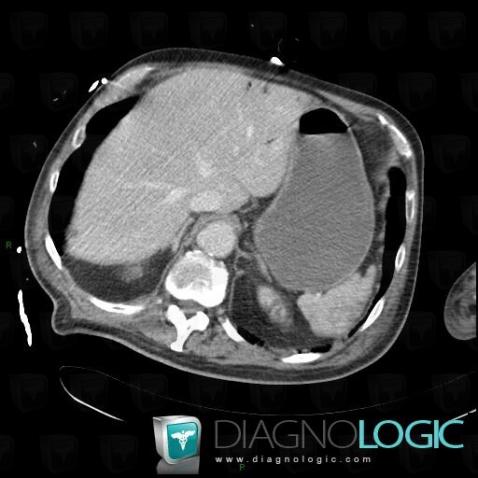

Portal venous gas, Portal vein and branches, CT

Here is the specific information in the key image above:

- Diagnosis Portal venous gas, Location(s) Portal vein and branches, with gamuts